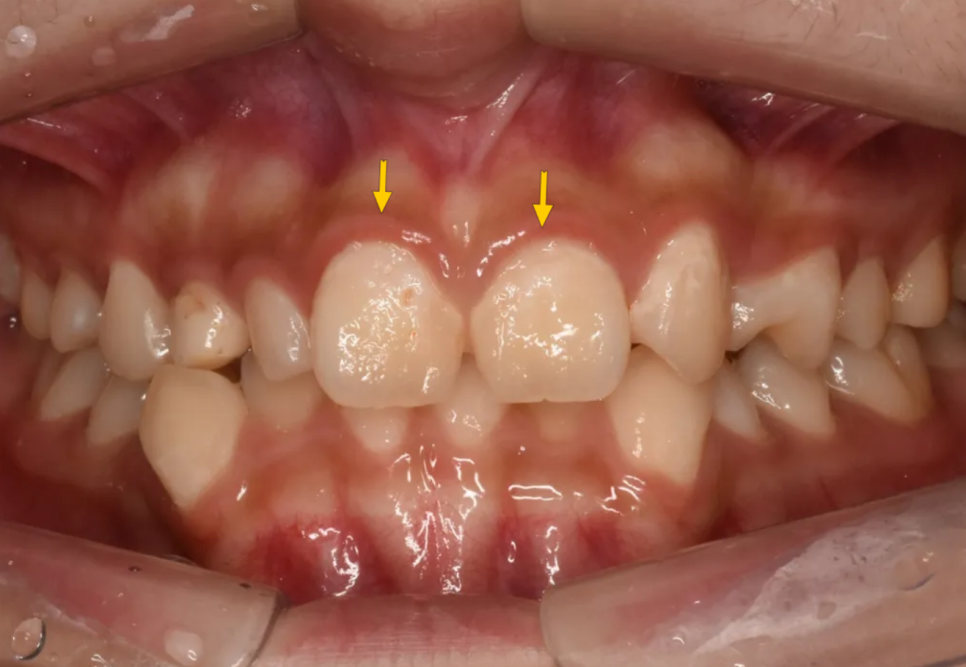

마지막으로 큰앞니 두 개의 모양이 다소 비심미적인 형태였습니다. 모양이 다소 예쁘지 못하고, 인접치아 대비 크기가 큰 편이었는데, 이는 위에서 언급된 다른 문제들만큼 심각하다고 할 수는 없지만, 심미적으로 바람직하지는 못한 형태였다고 할 수 있습니다.

첫번째로 가장 눈에 띄는 것은 사이즈가 유난히 작은 치아들이 존재하는 것입니다. 아래 그림에서 붉은색 화살표는 초등학교때 빠졌어야 할 유치(젖니)가 빠지지 않고 아직 남아있는 경우(유치잔존)입니다. 그래서 다른 치아들(영구치)보다 크기가 작은 것입니다. 노란색 화살표는 선천적으로 이가 작게 태어나는 "왜소치"인 경우입니다.